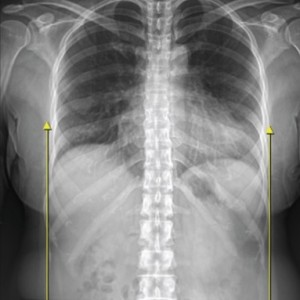

01.

척추

척추측만증 또는 좌, 우 한쪽으로 기울어진 척추로 인해 체중이 한쪽 허리로 집중된다면 장기적으로 체중이 기울어진 쪽 허리에 뼈가 자라거나 퇴행성 변화가 빠르게 진행됩니다.